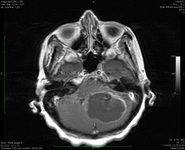

ნათხემის მწვავე ორმხრივი ინფარქტი დიფუზურ-შეწონილი მაგნიტურ-რეზონანსული ტომოგრაფიით

ექიმი ს.ჰ. საბრამონის კოლექციიდან; გამოყენებულია მფლობელის ნებართვით